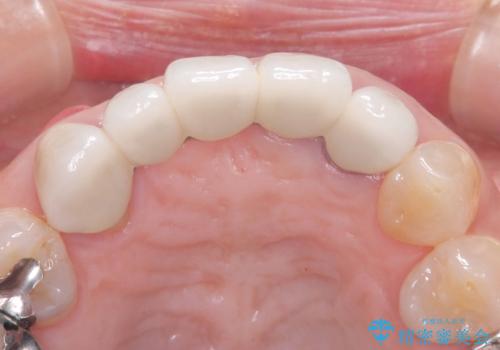

- 歯茎の大きな腫れを主訴に来院された患者様です。前歯5本にはブリッジが装着されていました。レントゲン検査より、右上3番に大きな根尖病巣が認められ、さらに左上1、2番の支台歯にも破折があったため、抜歯を行いました。その後、インプラントを3本埋入し、オールセラミッククラウンのブリッジで補綴しました。

術前のCT画像より、抜歯即時インプラントが可能と判断したため、抜歯と同時にインプラント埋入を行いました。術式にはセミルーナーフラップを用い、唇側の骨吸収を抑える目的でルートメンブレンテクニックを併用しました。

今回のケースでも、しっかりと固定が得られたため、手術は1回で終了し、短期間でオールセラミッククラウンまで装着することができました。患者様も術後の痛みはなく、処方した痛み止めも服用されなかったとのことです。

これだけ大きな病変があったにもかかわらず、痛みがなく短期間で治療が終わったことに加え、被せ物の色も周囲の歯に調和し美しく仕上がったことに、大変ご満足いただけました。